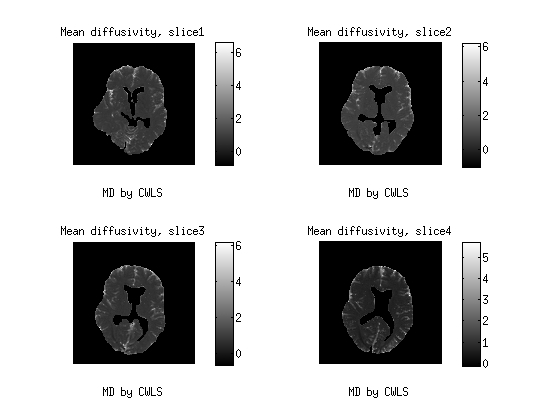

4.2 Real data

This data are part of a real experiment. It is consist of 2204 diffusion MR-images of the brain from an healthy human volunteer, taken from four 5mm5𝑚𝑚5mm-thick consecutive axial slices, and measured by a Philips Achieva 3.03.03.0 Tesla MR-scanner. The image resolution is 128×128128128128\times 128 pixels of size 1.875×1.8751.8751.8751.875\times 1.875 mm2𝑚superscript𝑚2mm^{2}. After masking out the skull and the ventricles, we remain with a region of interest (ROI) containing 187641876418764 voxels. In the protocol, we used all the combinations of the 323232 gradient directions with the b𝑏b-values varying in the range 0, 62, 249, 560, 996, 1556, 2240 s/mm2𝑠𝑚superscript𝑚2s/mm^{2} , with 333 repetitions, for a total of 7 242 904 data points.

In this session, we depict the results by MD Fig. 3, FA Fig. 4 as well as MK Fig. 5 from the proposed CWLS and MLE methods.The diffusion weighted MR data is in the range of (0, 581), acquired by 32 distinct gradient directions with seven different b values. After comparison, we can see that the image constrasts by the MLE method gain much more detailed structural information, especially in Fig.4 and Fig. 5 than those by the CWLS in the same scales.

Figure 3: 3d maps of MD by the CWLS and the MLE methods from four consecutive slices of human brain.The MD maps were scaled between (0,6) ×103mm2/sabsentsuperscript103𝑚superscript𝑚2𝑠\times 10^{-3}mm^{2}/s.